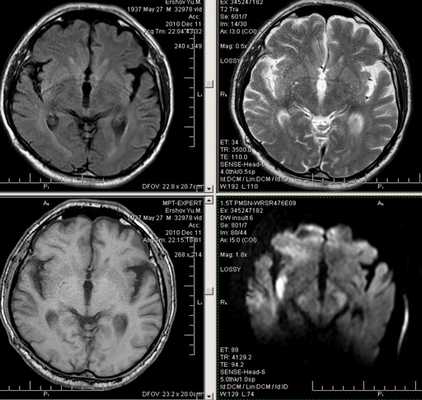

Первые часы ОНМК. Изменения в области правого островка демонстрирует только программа DW insult.

Зона подострого ишемического НМК, в бассейне правой средней мозговой артерии. В режиме Т1 визуализируется симтом «вуалирования»- изоинтенсивность МР-сигнала.